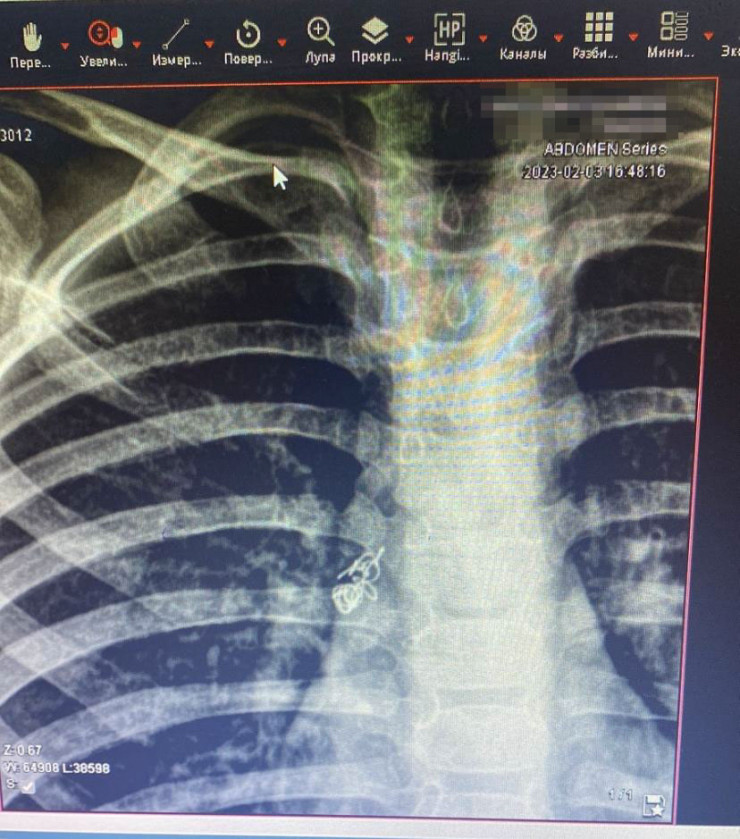

"Ребенок осмотрен специалистами, проведена рентгенография грудной клетки. На рентгенограмме выявили инородное тело правого бронха. Он был госпитализирован, проведена подготовка к манипуляции. Под общим наркозом проведена жесткая трахебронхоскопия. Под визуальным контролем инородное тело (пружинка) обнаружено в правом главном бронхе", - сообщили в пресс-службе ДГКБ № 2.

Специальным зажимом "крокодил" пружина была удалена. Ребенка выписали из больницы через четыре дня.